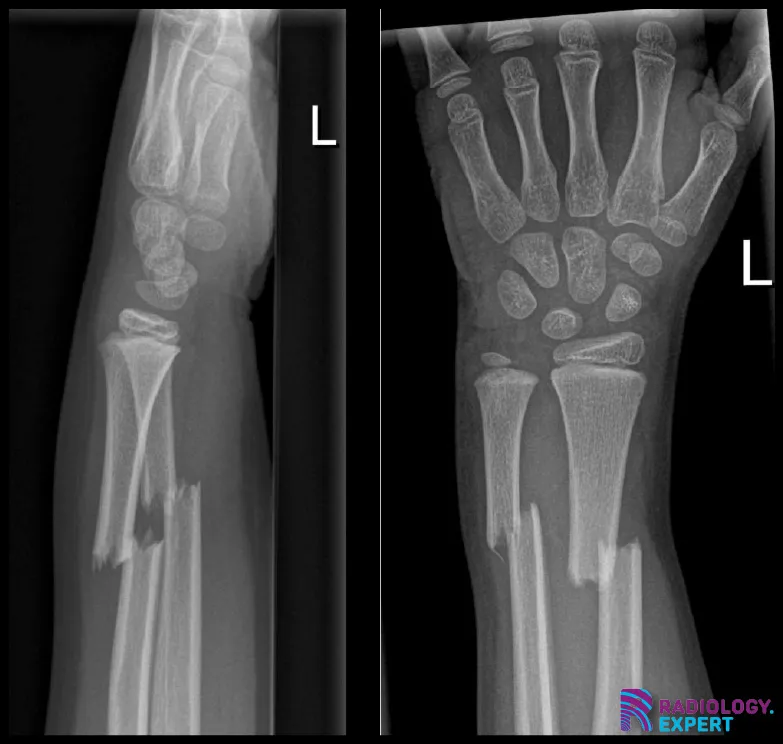

Figure 1. Lateral and anteroposterior view of the left forearm/wrist. A child (9 years old) with a distal radius shaft and ulna shaft fracture. Both show dorso-ulnar displacement of approximately one shaft width.